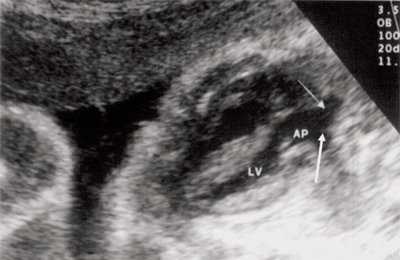

Рабдомиомы - самые частые опухоли сердца у детей. В 50-80% случаев они сочетаются с туберозным склерозом. Гистологически представлены крупными веретеновидными вакуолизированными клетками с большими запасами гликогена, сдвинутым на периферию ядром и гранулярной цитоплазмой. Макроскопически рабдомиомы нередко множественные, серо-желтого цвета, размером от мелкой горошины до гигантского относительно сердца узла, поражают стенки камер сердца и перегородки, могут распространяться как в полость желудочка (рис. 1), так и экстракардиально (рис. 2).

Рис. 1. Опухоль сердца (обозначена маркерами), исходящая из межжелудочковой перегородки в полость левого желудочка.

Рис. 2. Опухоль левого желудочка, распространяющаяся в основном экстракардиально и исходящая из стенки левого желудочка с переходом на межжелудочковую перегородку.